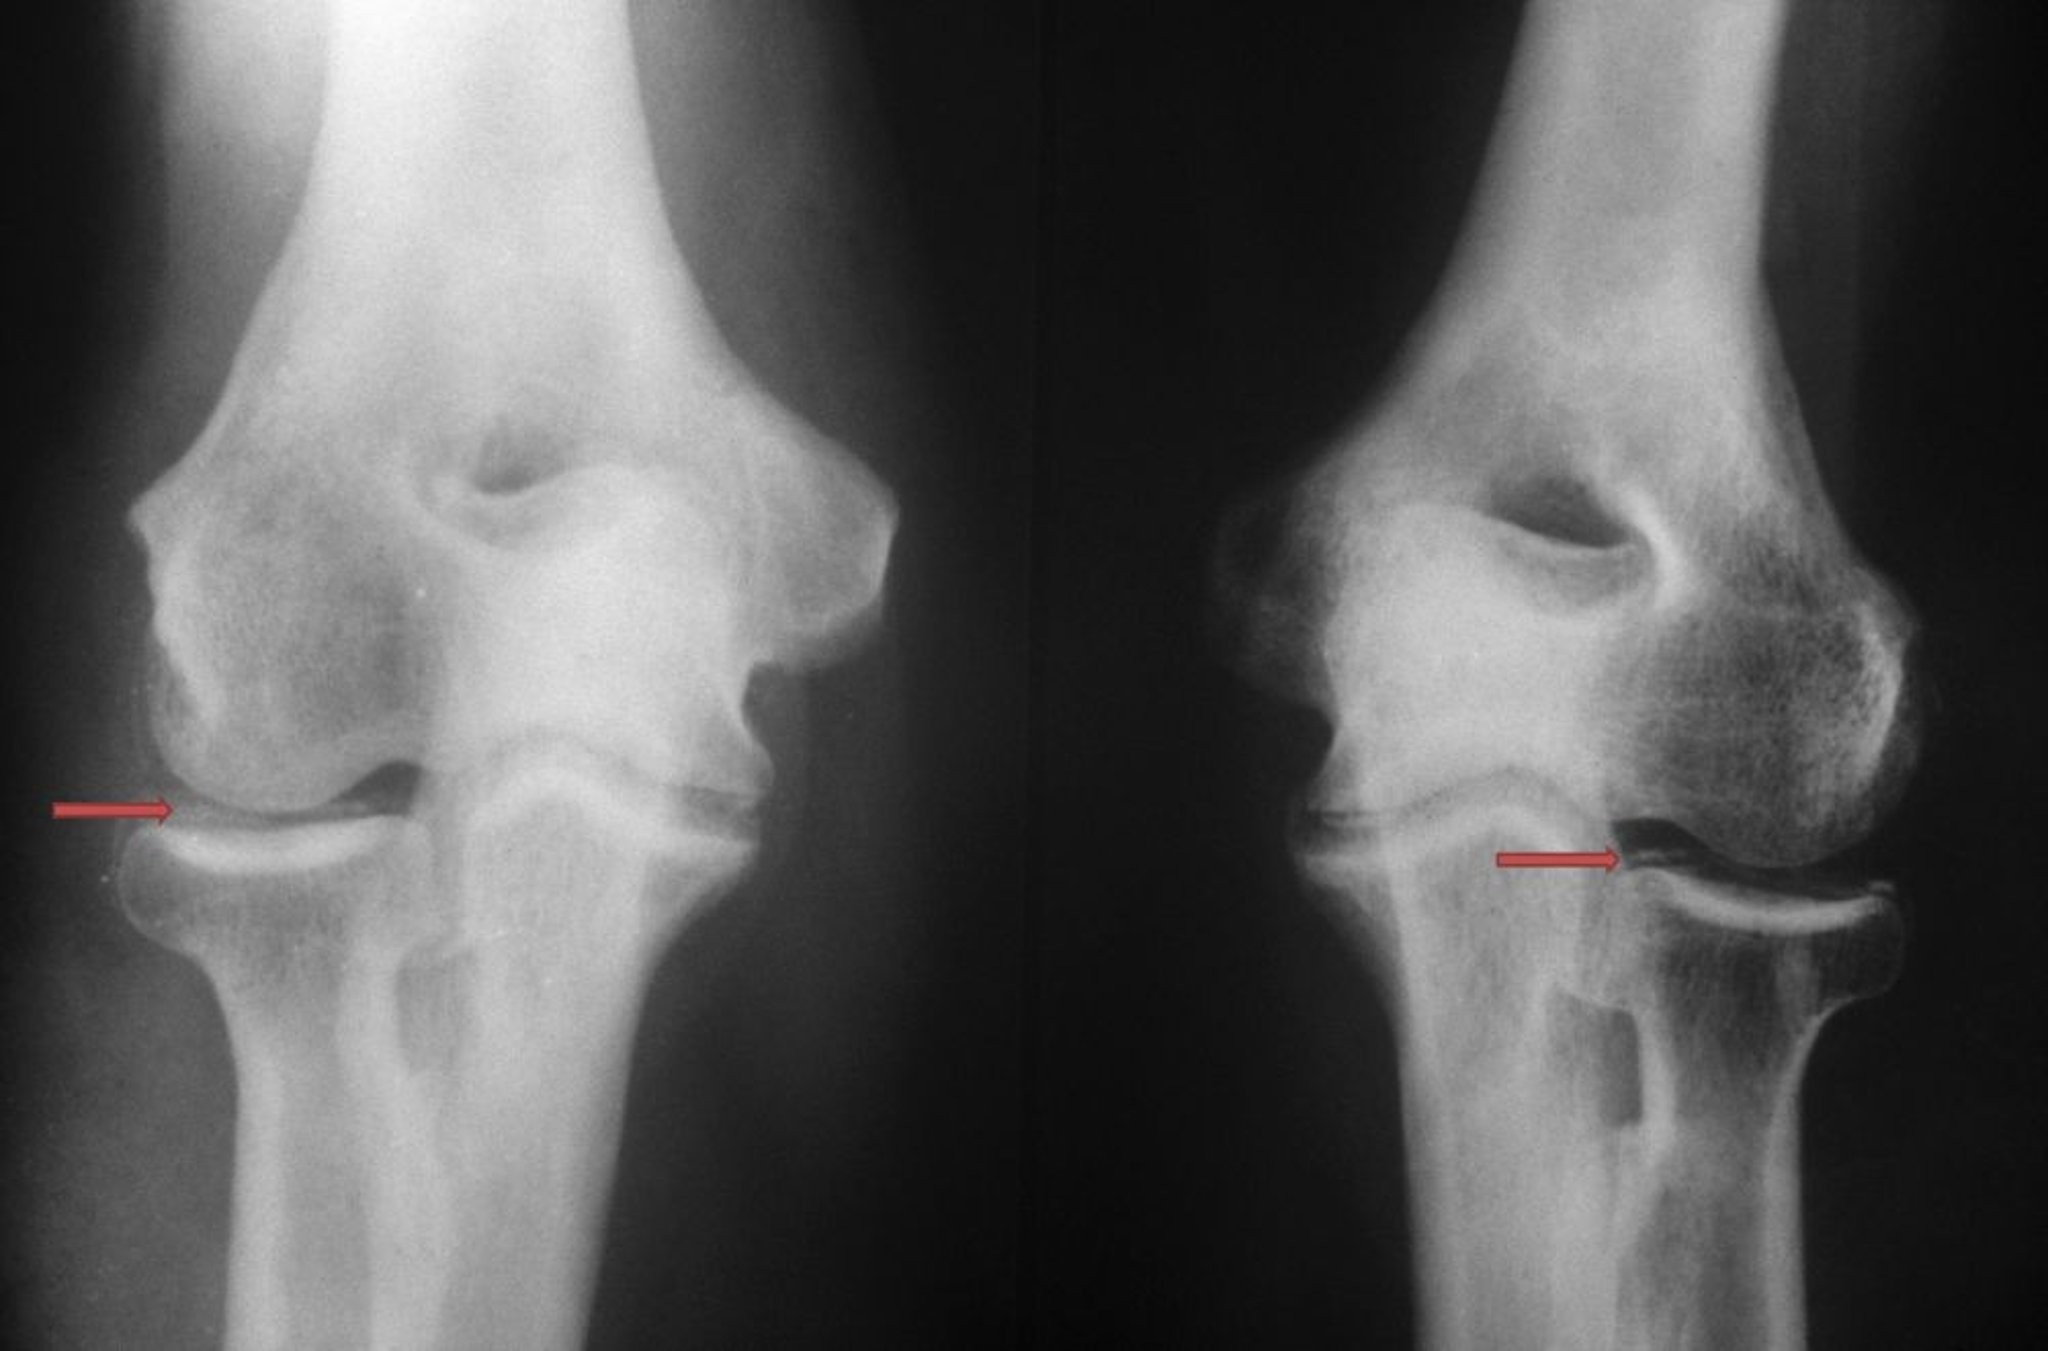

Enfermedad por depósito de pirofosfato de calcio

El depósito de cristales de pirofosfato de calcio es visible como radiopacidades densas mal definidas y de forma variable (flechas rojas) dentro de la articulación del codo.